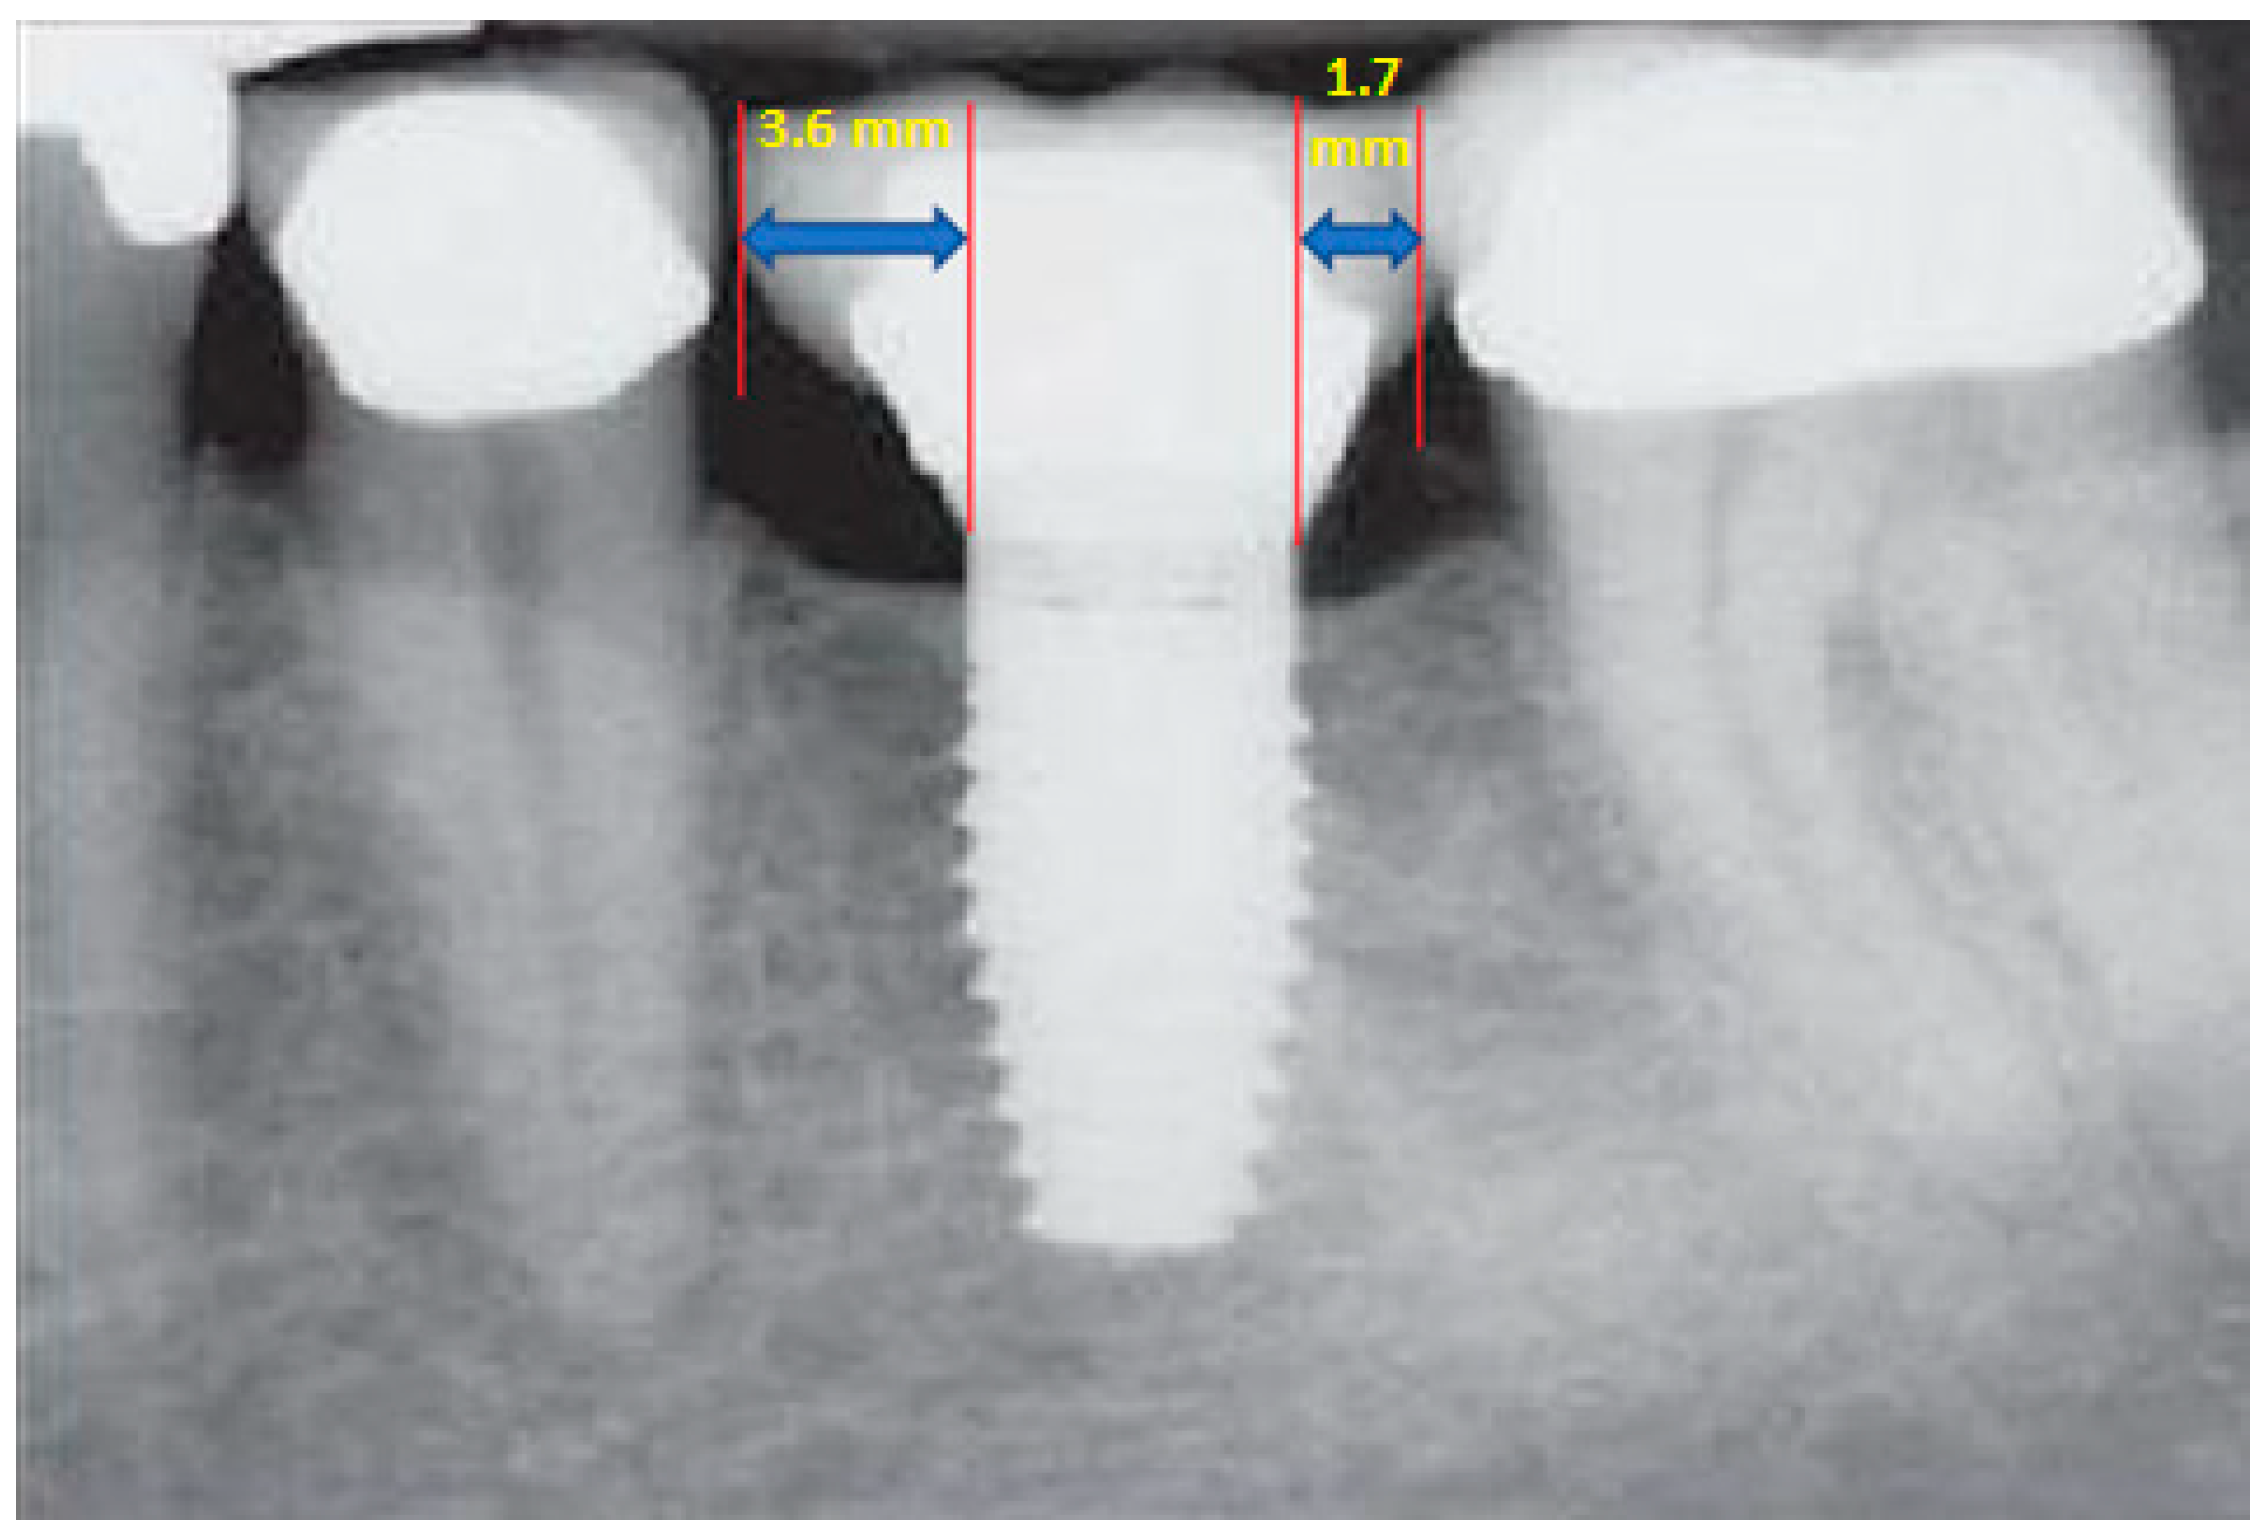

- Measurement of mesial and distal bone loss: Clinically, an increase in the probing depth of the peri-implant pockets, both mesial and distal, was recorded using a calibrated probe with a force of 0.25 N. Radiographically, mesial and distal peri-implant bone height loss was measured using properly performed radiological projections. In fewer than five patients, statistically significant findings in cases of bone loss were difficult to achieve.

- Measurement of the mesial and distal cantilever: The mesial cantilever was significantly greater for the bilateral bone loss group (1833.5 ± 1531.4 µm) compared to the group without MBL (1029.5 ± 968.6 µm) (F = 2.77; p < 0.05). Concerning the effect of the mesial versus distal cantilever, although the mesial cantilever appears to be more favorable, the only article found in the literature regarding this finding is a study by Romeo et al. (2003), which showed that this effect is not always consistent, although the difference is minimal [31].